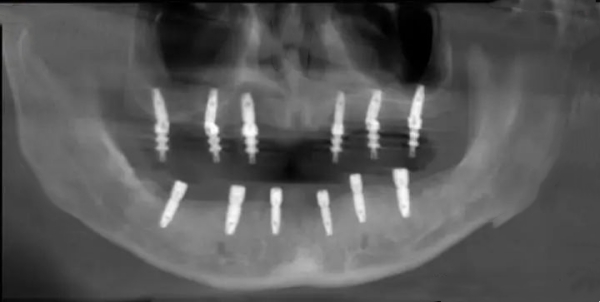

CBCT可以重建出你口腔的三維立體圖像,醫(yī)生可以清楚地測(cè)量頜骨的高度、寬度、密度,評(píng)估牙槽骨條件,判斷是否需要植骨。CBCT的線性測(cè)量精度可達(dá)到0.1毫米級(jí)別,與被檢查物之間比例接近一比一,能夠滿足種植手術(shù)的穩(wěn)準(zhǔn)規(guī)劃需求。

根據(jù)2024年發(fā)布的《數(shù)字化種植導(dǎo)板手術(shù)的精細(xì)性醫(yī)生共識(shí)》,要實(shí)現(xiàn)高精度種植,需要做到:選擇合適的導(dǎo)板類型、規(guī)范數(shù)據(jù)采集流程、優(yōu)化計(jì)算機(jī)輔助設(shè)計(jì)、改進(jìn)計(jì)算機(jī)輔助制作。中諾口腔在這些環(huán)節(jié)都有成熟的流程把控。